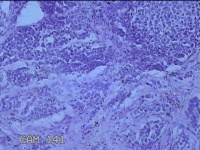

性别

男

年龄

48岁

临床诊断

皮下结节

一般病史

发现前额部结节半年余。

标本名称

前额部结节

大体所见

灰白暗红色0.8x0.3x0.2cm一块,表面带梭形皮肤0.8x0.3cm,皮下见结节0.7x0.3x0.2cm一个,切开结节呈实性,切面灰白粉红色,质软。

图2